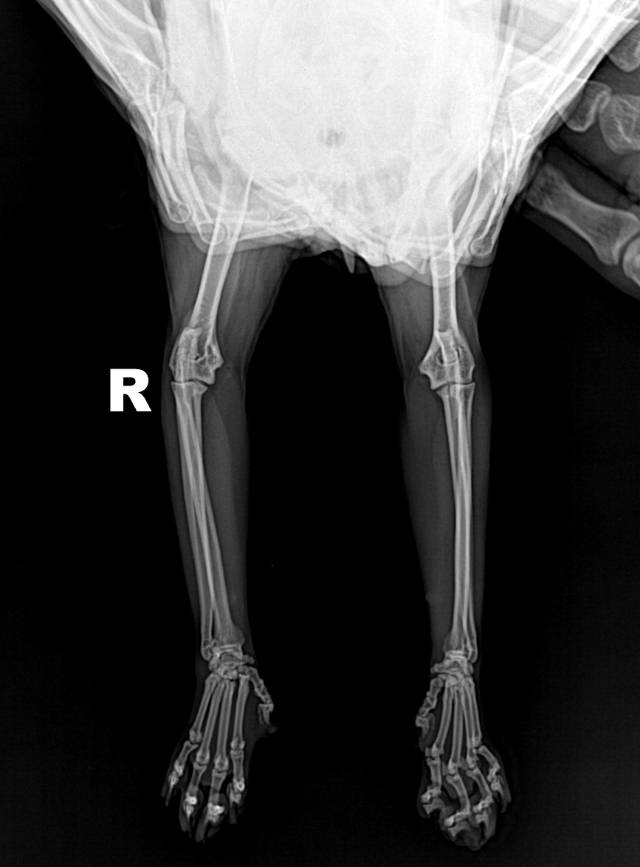

昨天晚上从高处跌落(两米多左右高度),目前前爪(右边)肿了,走路到现在还是一瘸一拐,能吃能喝。拍了X光片,可以帮我看下吗?没有骨折,是否有骨骼错位没看出来?

医生您好,我家孩子这几天走路一瘸一拐的,出院之后到现在还不会,这个是前几天带他拍的片,医生说右脚恢复得不是很好,开了止痛药,我想知道这种情况他会不会持续性疼痛?平时要出来走呢还是静养比较好?因为这个孩子太调皮了,早上放出来走走他直接就开始跑,吓得我赶紧抱回笼子里…萌宠医5530 | 图文问诊 | 2025.06.18 10:01:22